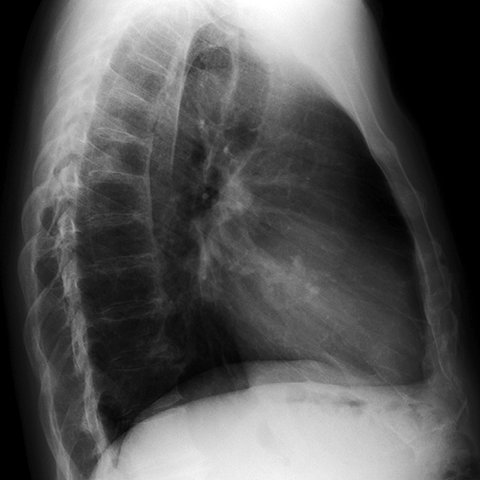

Aortic Stenosis [2 of 2]